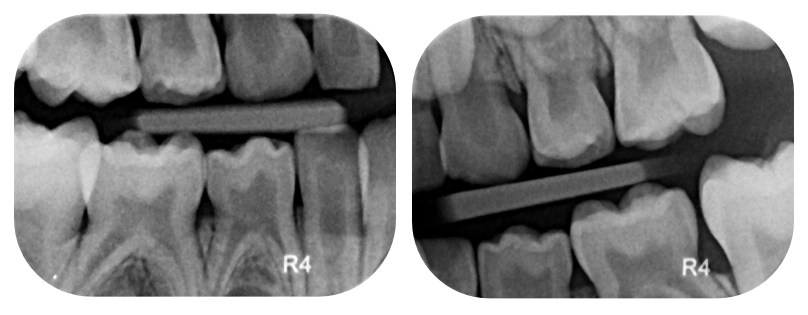

- Intraorálne a zhryzové snímky: Tieto malé detailné snímky zhotovujeme individuálne podľa potreby. Sú kľúčové pre odhalenie medzizubných kazov, ktoré voľným okom nie sú viditeľné.